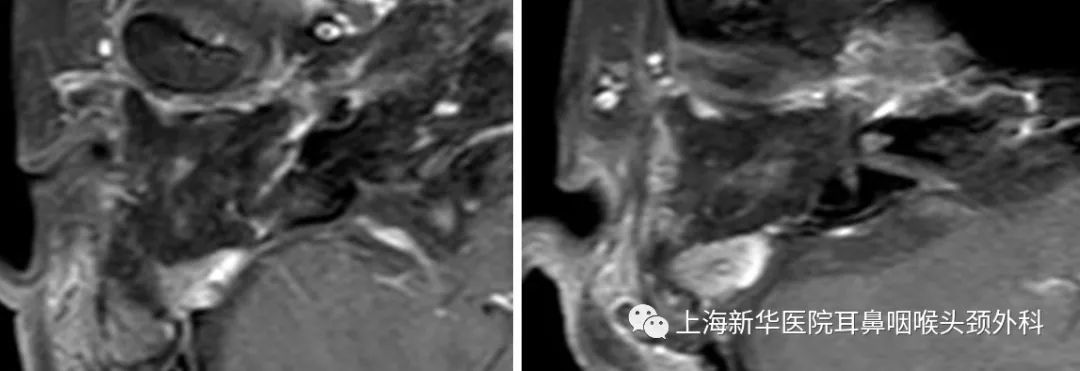

术后CT:

术后增强MRI: